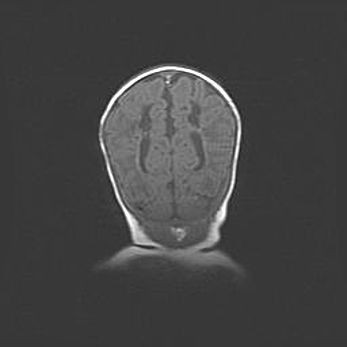

Множественные кисты обоих полушарий головного мозга, наибольшая из них в правой затылочной области. Ассиметричная атрофическая гидроцефалия.

Возраст: 7 месяцев

Вес: 5660 г

Пол: мужской

Окружность головы: 41,5 см

Срок гестации: 28-29 недель

Кисты головного мозга развиваются в результате многоочаговых некрозов вещества мозга и возникают вследствие перенесенной перинатальной инфекции, менингитов, энцефалитов, асфиксии, родовой травмы, расстройств мозгового кровообращения различного генеза. Образованию кист в веществе головного мозга плодов и новорожденных способствуют такие факторы, как высокое содержание в нем воды, недостаточная (или отсутствие) миелинизация и слабая астроглиальная реакция на повреждение.

Кисты могут сочетаться с гидроцефалией и другими поражениями головного мозга.